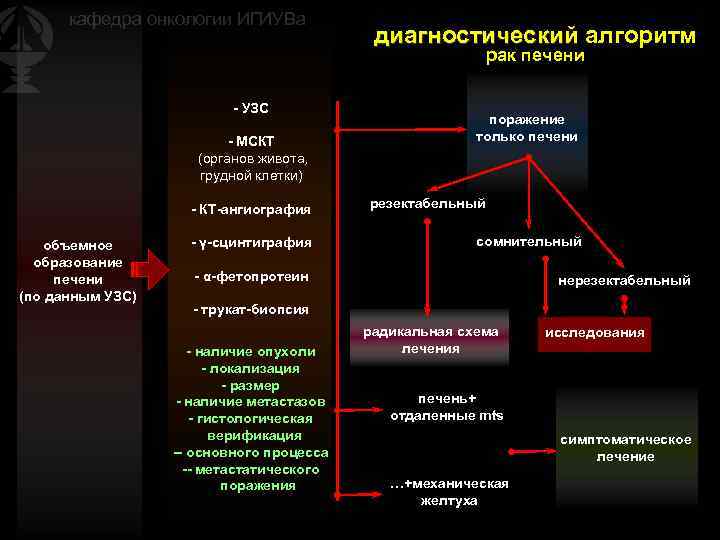

Метастатические поражения печени в ультразвуковом изображении характеризуются